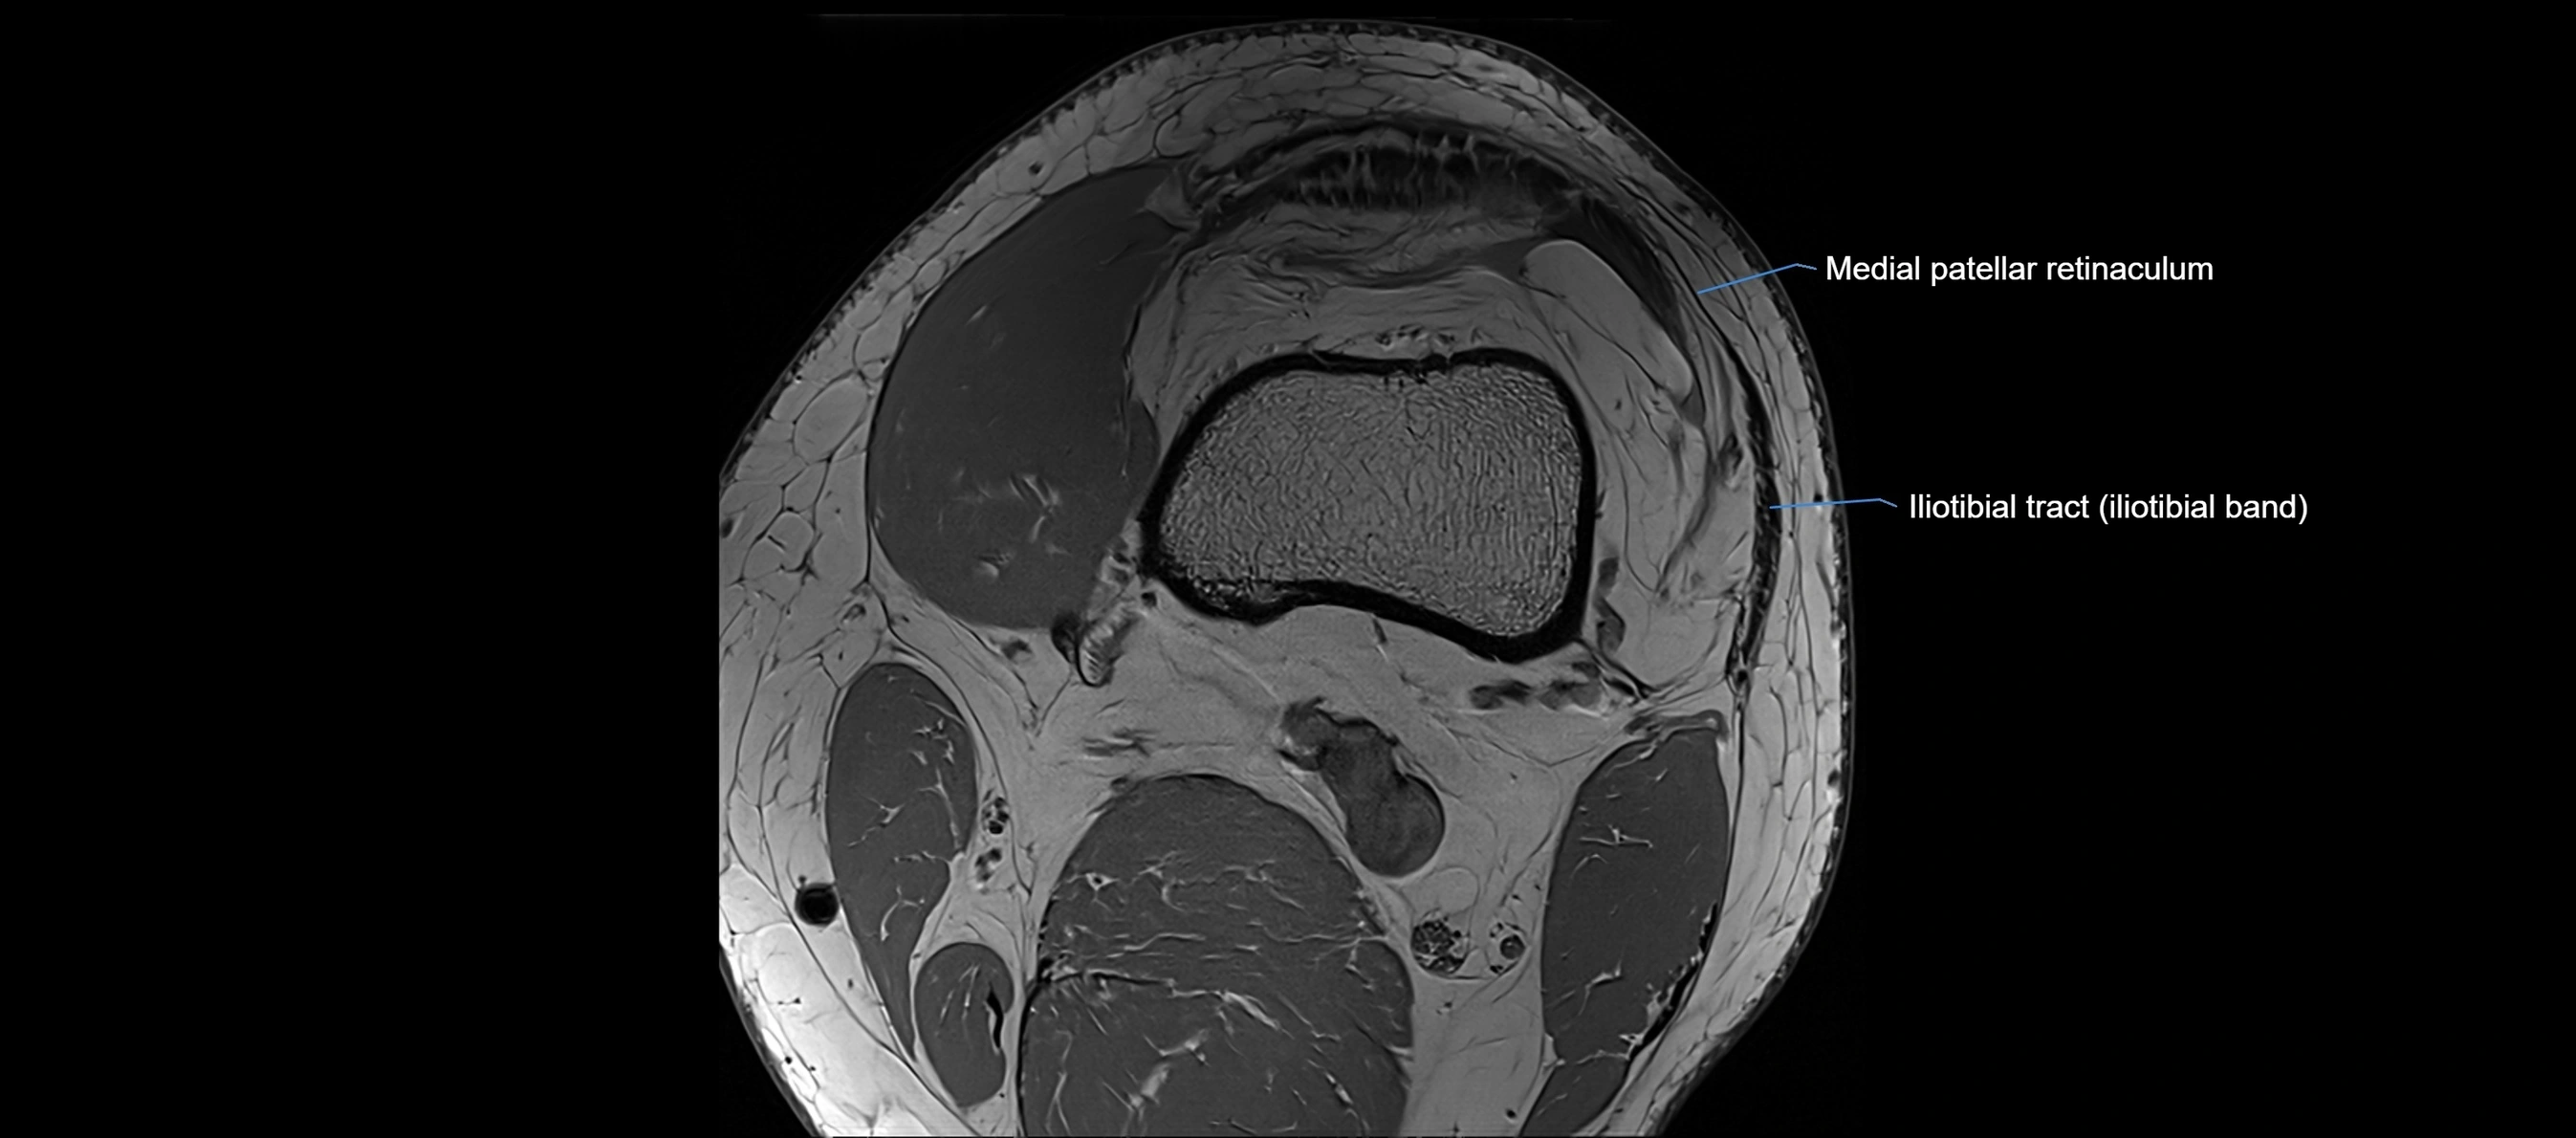

MRI images

image